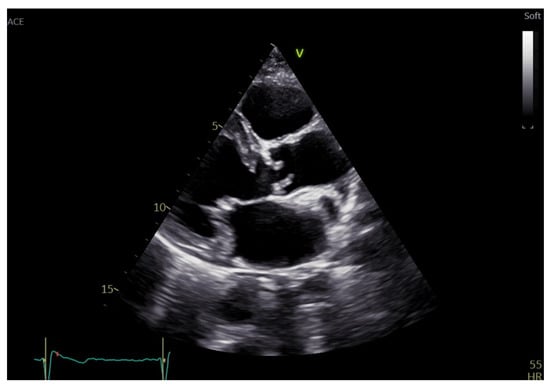

2. Aortic Stenosis Etiology and Echocardiographic Morphologic Assessment

3.2. Role of 3D Echocardiography in the Evaluation of Aortic Stenosis